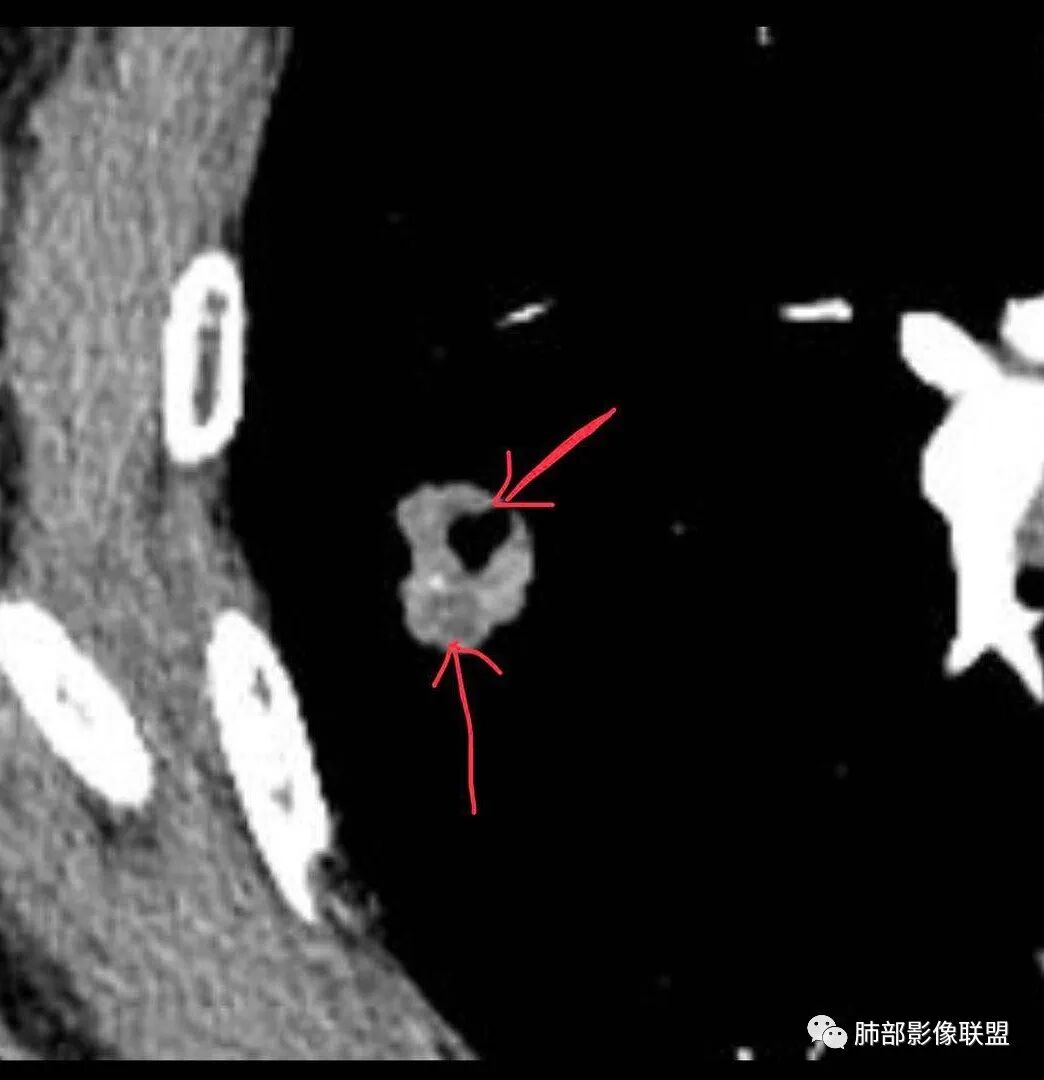

我觉得搞清楚空洞还是空泡也很重要,空泡指向癌,空洞癌、结核、PC都可以

就这一例而言我也不知道是空泡还是空洞,感觉不具有形成空洞的病理基础(坏死物经支气管排出);所以一开始就请教老师了

毛勤香:

不像空泡,有点鬼脸的感觉,增强坏死多,但毛刺也多

空泡是绕正常的肺组织或支气管生长形成,空洞是实性组织坏死,坏死物排出所致。但这么小不好区别。

@毛勤香 柳州龙潭医院影像 毛老师,是因为其内空腔不规则,考虑空洞吗?

再加上增强其内有坏死,考虑这个是空洞吗?

@任广国 双鸭山市人民医院影像 我理解的空泡是扩张的截断的支气管断面或肺泡活瓣作用的扩大

空泡征包括两部分:未被肿瘤侵犯的肺泡组织,也可能是贴壁为主的癌组织,并不完全是肺组织